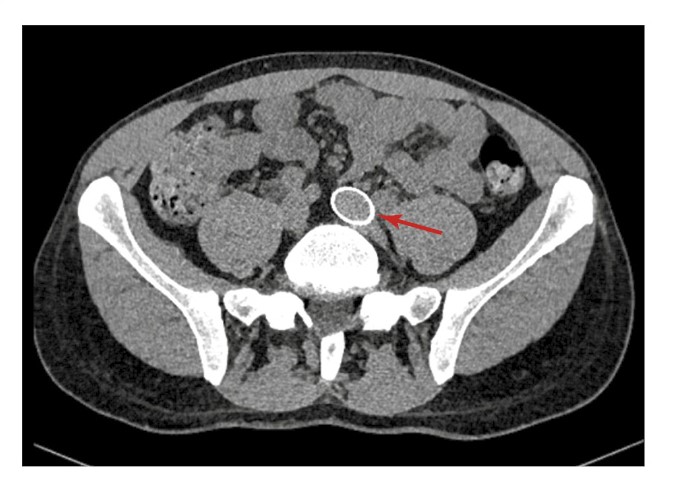

В левой общей подвздошной вене с выходом в нижнюю полую вену определяется стент (рис. 3).

Рис. 3. Данные МСТК-кавернозографии больного К. Стрелкой указан стент в левой общей подвздошной вене.

Размеры, форма и ход кавернозных тел обычные. Отток контрастного препарата нарушен. На 30-й секунде определяется наличие минимального сброса контрастного препарата в перипростатическое сплетение через вену левой ножки ПЧ. На 1-й минуте отмечаются умеренное контрастирование вен в области левой ножки ПЧ и существенный сброс контрастного препарата через вены правой ножки ПЧ и вены тазового сплетения справа (рис. 4).

На 5-й минуте сохраняются описанные патологические венозные дренажи без существенной динамики. 3D-реконструкция КТ-картины нарушения вено-окклюзионного механизма ПЧ приведена на рис. 6. Отмечены резкий венозный сброс справа и умеренный венозный сброс слева.

Рис. 6. 3D-реконструкция КТ-кавернозографии. Стрелками указаны значительный сброс контрастированной крови из кавернозных тел через венозный коллектор простатического сплетения в правую общую подвздошную вену (3–5-я минута после введения контрастного препарата).